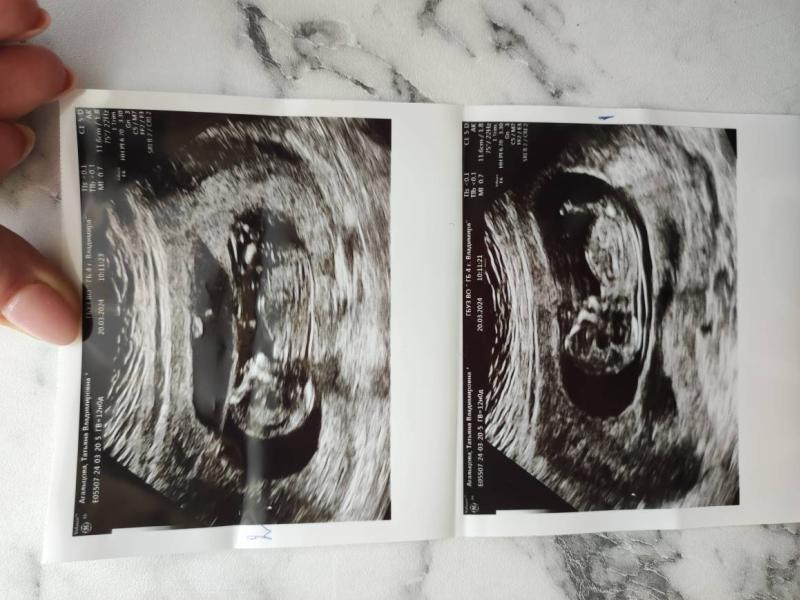

Сегодня был скрининг. Ровно в 12недель, но мои шилопопы на неделю крупнее😁 даже не получилось разглядеть пол, т.к ооочень сильно вертелись) главное что по узи они полностью здоровы, кровотоки все тоже отличные. Пока идем хорошо. Назначили узи на 11апреля, посмотреть шейку и узнать пол лялек)